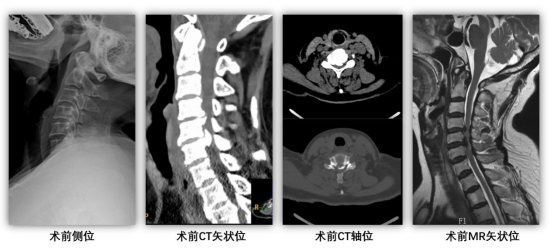

患者辗转多家医院,确诊为颈椎后纵韧带骨化症、脊髓型颈椎病。影像学检查显示,患者颈5-6 节段后纵韧带骨化严重,膨隆的脊髓被压迫至不足正常的 1/3,脊髓受压极重,脊髓症状明显,此前患者因恐惧手术放弃治疗,理疗后症状持续加重,5 天后毅然重返我院,决心接受手术根治。

术后恢复效果立竿见影,四肢麻木症状快速缓解,困扰许久的腰腹部束带感完全消失;次日即可下床活动,行走不稳、踩棉感显著改善,肢体力量逐步恢复。复查影像椎管减压效果显著,脊髓顺利膨隆,手术达到预期治疗目标。